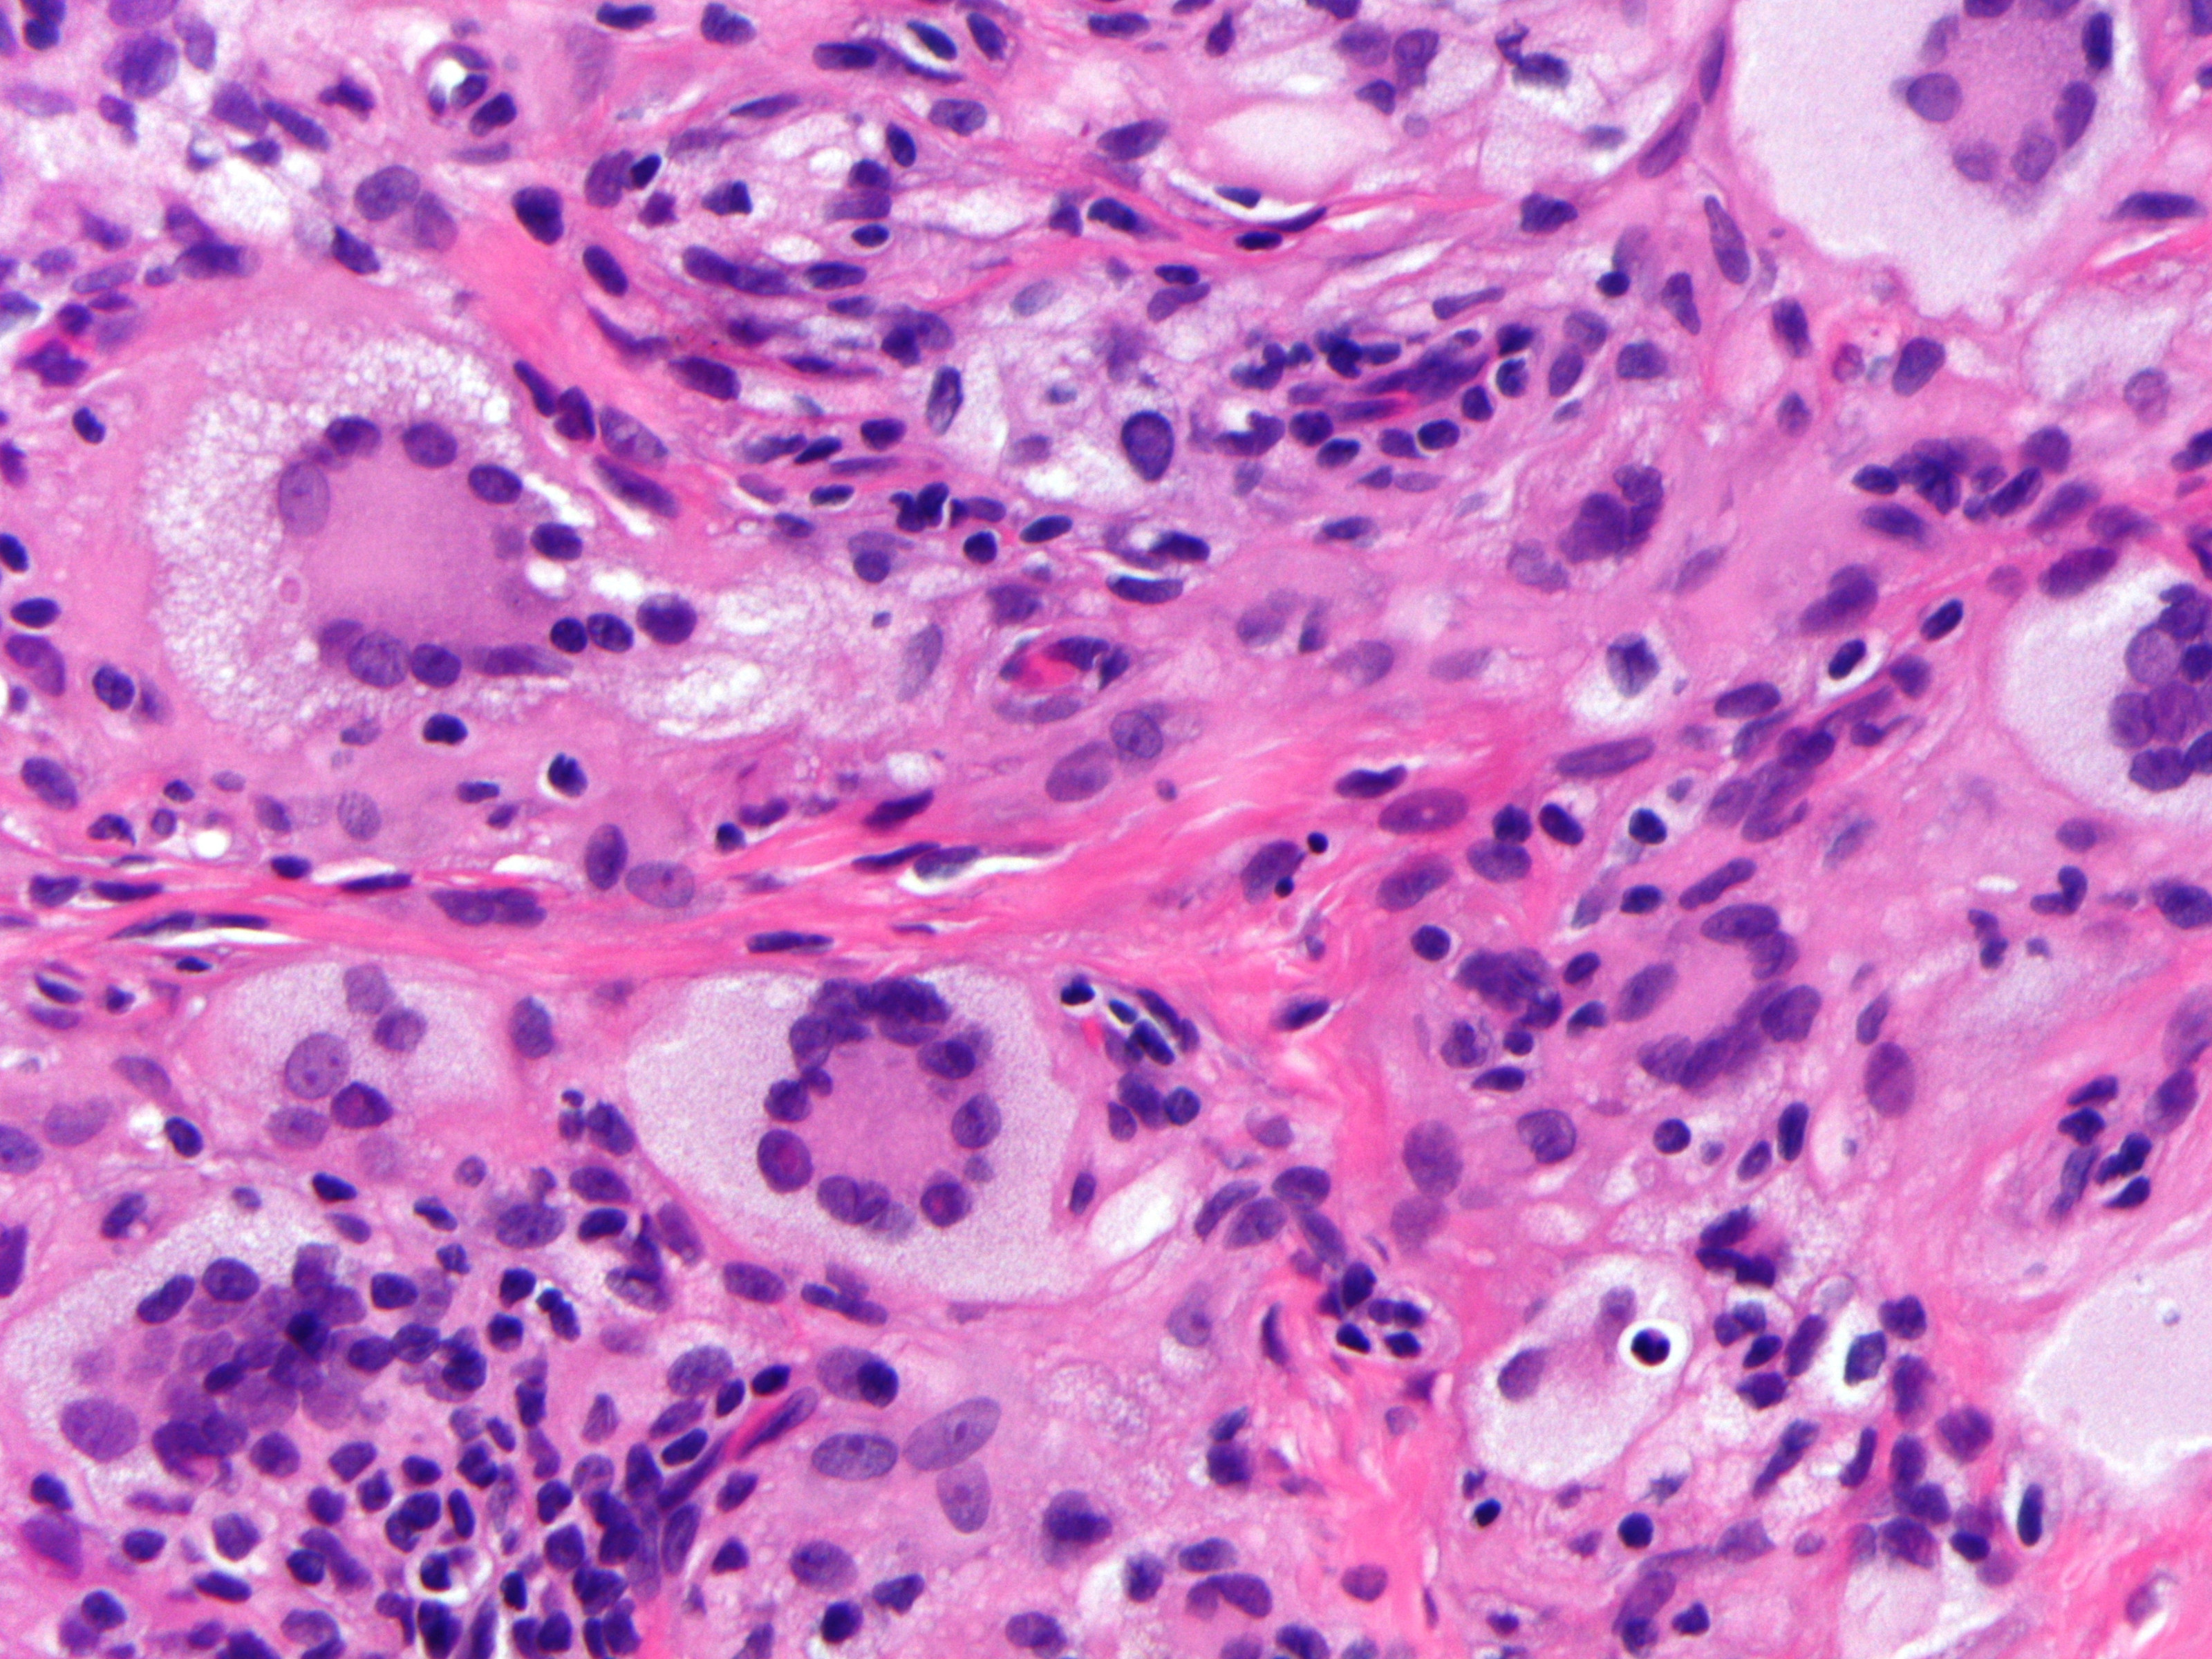

Infiltraat in de dermis bestaande uit histiocyten met een gevacuoliseerd, schuimig cytoplasma en ronde tot ovale kernen met een enkele nucleolus, en vaak met karakteristieke Touton-reuscellen. Daarnaast zijn er in wisselende mate reuscellen, lymfocyten en eosinofiele granulocyten aanwezig. Bij elektronenmicroscopisch onderzoek ontbreken de Birbeck-granula die typisch zijn voor de Langerhans-celhistiocytose. Bij vroege stadia kunnen de Touton-reuscellen en het schuimige aspect van het cytoplasma ontbreken. De cellen kleuren aan met de markers CD68, humaan macrofaag antigeen (HAM) 56 (een epitoop van CD68), factor XIIIa, cathepsine B, KiM1P (een pan-macrofaagmarker), KP1 (een epitoop van CD68) en vimentine, terwijl ze negatief zijn voor S100, CD1a en de macrofaagmarker Mac387.

Histologie juveniel xanthogranuloom Histologie xanthogranuloom

ingescande coupe (zoom) ingescande coupe (zoom)

Histologie xanthogranuloom Histologie xanthogranuloom

PA-Foto's boven: Michael Bonert (Nephron) - Wikimedia (Creative Commons License 3.0)

Hoge resolutie PA-foto's: Kevin Kwee en Afdeling Pathologie MUMC. Klik op de afbeelding om in te zoomen.